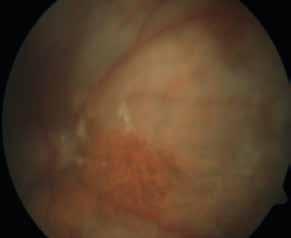

Type 2 MNV refers to the proliferation of new vessels originating from the choroid into the subretinal space. These vessels penetrate through the sub-RPE, making the subretinal portion the dominant component of the pathological process in Type 2 neovascularization. On FA, these lesions are usually “well-defined” as they present a well-demarcated area of hyperfluorescence in the early phase of the angiogram, followed by progressive dye pooling in the overlying subsensory retinal space during the late phase. (Figure 2)

Figure 2. Multimodal imaging of Type 2 macular neovascularization. Infrared reflectance (A) and fundus autofluorescence (B) revealing abnormalities of retinal pigment epithelium. Early and late phase of indocyanine green angiography (C and D) and fluorescein angiography (E and F) showing a well-defined neovascular network. Optical coherence tomography angiography (G) displaying the neovascular network. Optical coherence tomography (H) showing the neovascularization above the retinal pigment epithelium with disorganization of the overlying inner segment/outer segment junction.